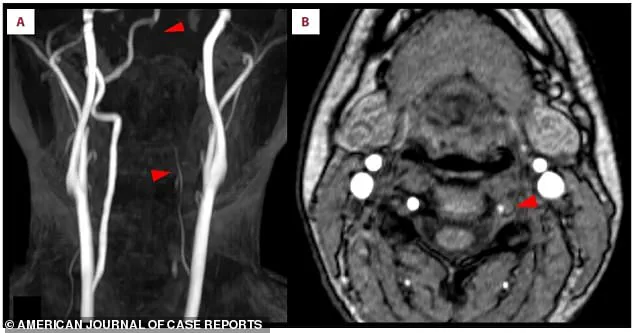

Doctors discovered that the repetitive overhead motions had placed extreme mechanical stress on a vulnerable artery in her neck, leading to a tear in its inner lining—a condition known as vertebral artery dissection (VAD).

This tear allowed blood to seep into the artery wall, creating a clot that narrowed the passageway and eventually traveled to her brain, causing an ischemic stroke.

The clot, which formed due to the VAD, lodged in a critical blood vessel supplying the brain’s vision center, cutting off oxygen and resulting in left-sided vision loss and numbness.

In this case, the clot originated from the tear in the left vertebral artery, a condition that affects approximately one to 1.5 Americans per 100,000 annually.

The scans also pointed to a critical issue in the left vertebral artery, a key blood vessel in the neck.

It appeared faint and thin, suggesting chronic narrowing that had likely gone unnoticed until this emergency.

The final piece of the puzzle was a crescent-shaped blood clot embedded in the artery’s wall, the direct cause of the blockage.